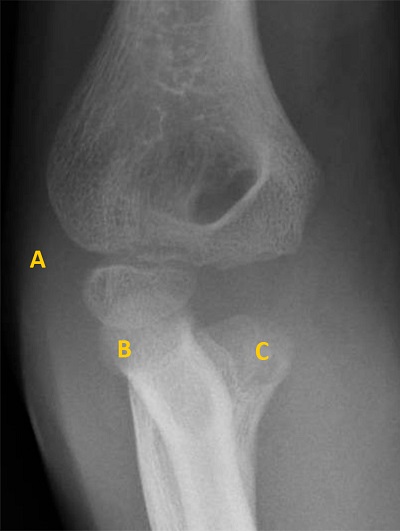

1. Paciente de 7 años con dolor en codo derecho tras caída. Presenta dolor y limitación a la flexo-extensión. Se realiza radiografía (Figura 2) que se informa como normal, diagnosticándose de fractura de epitróclea a los 3 días.

Figura 2. Fractura de epitróclea

A: capitellum; B: cabeza de radio; C: epitrócela avulsionada.

La radiografía muestra capitellum y cabeza del radio. No se identifica el núcleo de la epitróclea que le correspondería tener por edad. Además, próxima a la cabeza de cúbito se encuentra una imagen hiperdensa redondeada: se trata del núcleo de la epitróclea avulsionado.